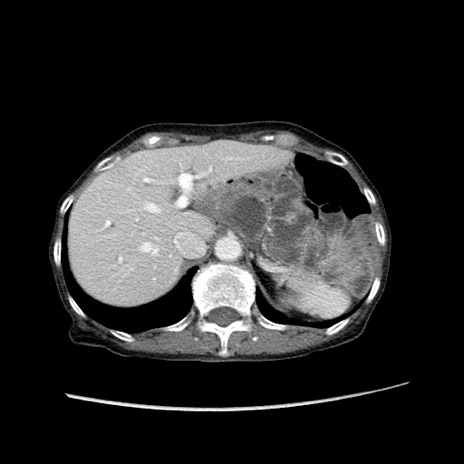

症例25(横断像)

【症例】80歳代女性

【主訴】胸のつかえ感

【現病歴】約9時間前に食後から胸のつかえた感じあり、嘔吐あり、来院。

【既往歴】胃癌(全摘)、胆摘、虫垂炎

【身体所見】心窩部に圧痛あり、反跳痛なし。

【データ】WBC 5700、CRP 0.05